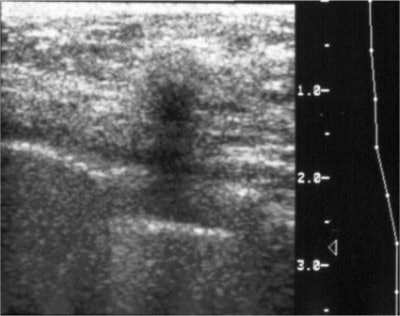

![]() |

| A large cancer is present in the image on the left, but the cancer cannot be seen because it is completely obscured by the dense glandular tissue around it. Note that the breast with the cancer looks exactly like the one without a cancer. The cancer was found here because it was palpable, and was visible on an ultrasound done at the same time as the mammogram. Image courtesy of Dr. Michael Linver. |

Ultrasound should not be ruled out in the young breast, though, said Linver. "If the patient is under 30, ultrasound would be the place to start," he said. "We can find breast cancers sometimes on ultrasound that we can’t find on mammography."

| Cancers on ultrasound are usually dark and more easily seen on a background of dense tissue (white). Image courtesy of Dr. Thomas Kolb. |